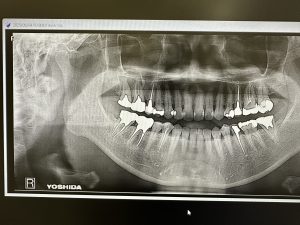

巨大病巣

根管治療開始3カ月、患者さんは非常勤M先生の友人

初めは、動揺がある7番意図的抜歯し病巣掻爬し再植を考えたが

根管治療開始1カ月経過時点で動揺が治り、根管治療のみでやることにした

決めては

6箇所(6根)からのアプローチがキーポイント‼️